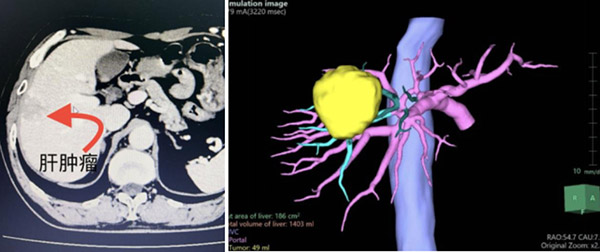

直径4厘米的肿瘤,不偏不倚长在了曾被视为手术“禁区”的肝脏顶部(S8段),这里血管、神经密集,暴露困难、大出血风险高,那么该如何既治愈疾病又保证病人的安全?近日,沈阳市第六人民医院(沈阳市肝胆外科医院)院长徐进教授亲自主刀,带领普外二科王玉文团队参照国际标准,联合应用荧光腹腔镜技术和术中超声完成一例肝S8段切除,安全、精准、高效地为病人解决了疾病困扰。这次勇闯“禁区”的成功,标志着市六院应用腹腔镜实施复杂的肝胆胰微创手术已成为常规化,医院对大型手术的承接能力以及微创化、高精准的诊疗技术,也达到了地区的领先水平。

通过一系列专业、完善的检查,徐进院长明确了肝癌的诊断。“早期诊断、早期采用以手术切除为主的综合治疗,是提高肝癌病人长期治疗效果的关键。从病人角度考虑,损伤小、恢复快的微创腹腔镜肝切除无疑是最佳选项,但由于丁先生病变的体积大,所在位置血管、胆管和神经密布,极易发生术中大出血,甚至危及生命,这给医生的操作和技术提出了非常高的要求。”在看过肝部影像、计算机3D模拟图像后,徐进院长说道。

42岁的丁先 生患慢性乙肝多年,最近体检发现肝脏顶部(S8段)占位性病变、甲胎蛋白升高,这些都与肝癌相关。于是他赶忙到家附近的医院接受了增强CT和增强磁共振检 查,结果显示为肝细胞癌,病灶直径达4厘米。作为一个老沈阳人,丁先生果断来到作为沈阳市肝癌诊治中心的市六院,向国内著名肝胆胰外科专家徐进院长寻求治 疗。